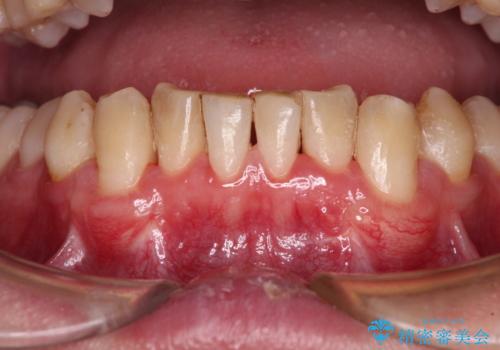

- 下顎犬歯の歯肉退縮を気にして来院された患者様です。

歯磨きの際にしみるとのことで、歯肉移植による根面被覆を行うこととしました。